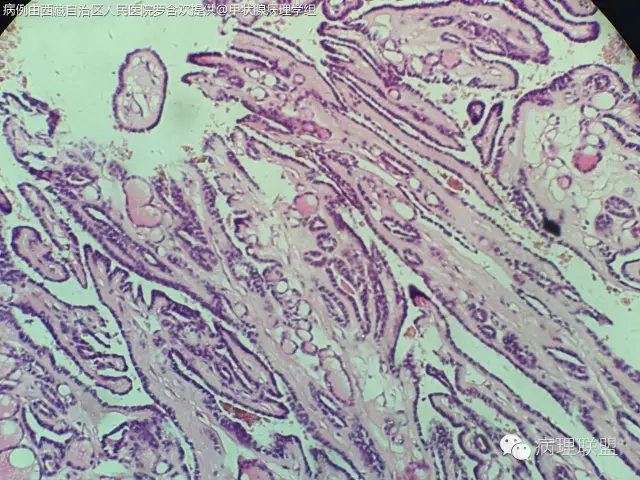

打脸病例分享,52/F,19年前因右侧甲状腺腺瘤行局部切除,因甲状旁腺功能亢进行甲状旁腺摘除,术中送检部分右侧甲状腺组织,冰冻切片未见异常,常规石蜡切片见乳头状结构,乳头间质见沙粒体,镜下图片如下:

自己在镜下看了半天核是有点挤,我们苏木素染色有点深,没看出有啥核沟和包涵体。因为出现沙粒体,上级医生不放心,加做免疫组化:

微小乳头状癌。这种结构有时看不到典型的核的特点。@毕超

@阳宇 我之前还觉得没有核特征不能下癌,这例的不典型是否和冰冻有关?我们染色有点深

嗯嗯。个人觉得跟冰冻有些关系,还待其他老师高见

第一例乳头内有滤泡,第二例是真正纤维轴心,两例乳头不一样

PTC.核已经出现拥挤参差不齐,卵圆形有异性,加上沙立体的出现标准已够。实际上出现沙立体意味着PTC.但是要区分滤泡腔内深染浓缩的胶质。还有PTC强调在正常滤泡背景中的突然性,两者不能有移形。